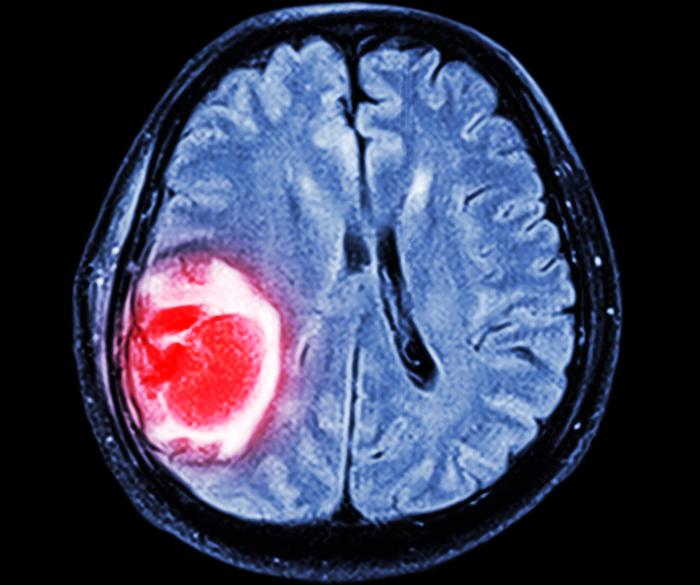

Un diagnostic de glioblastome du cancer du cerveau implique un pronostic très péjoratif, la plupart des patients mourant dans les cinq ans. Un espoir pour le traitement de masse du glioblastome est ouvert par une équipe dirigée par les chercheurs du Massachusetts General Hospital, à Boston : l'ajout d'hydroxyurée, un médicament déjà ancien, au protocole actuel de chimiothérapie augmente significativement la survie et la guérison, dans un modèle animal de glioblastome.